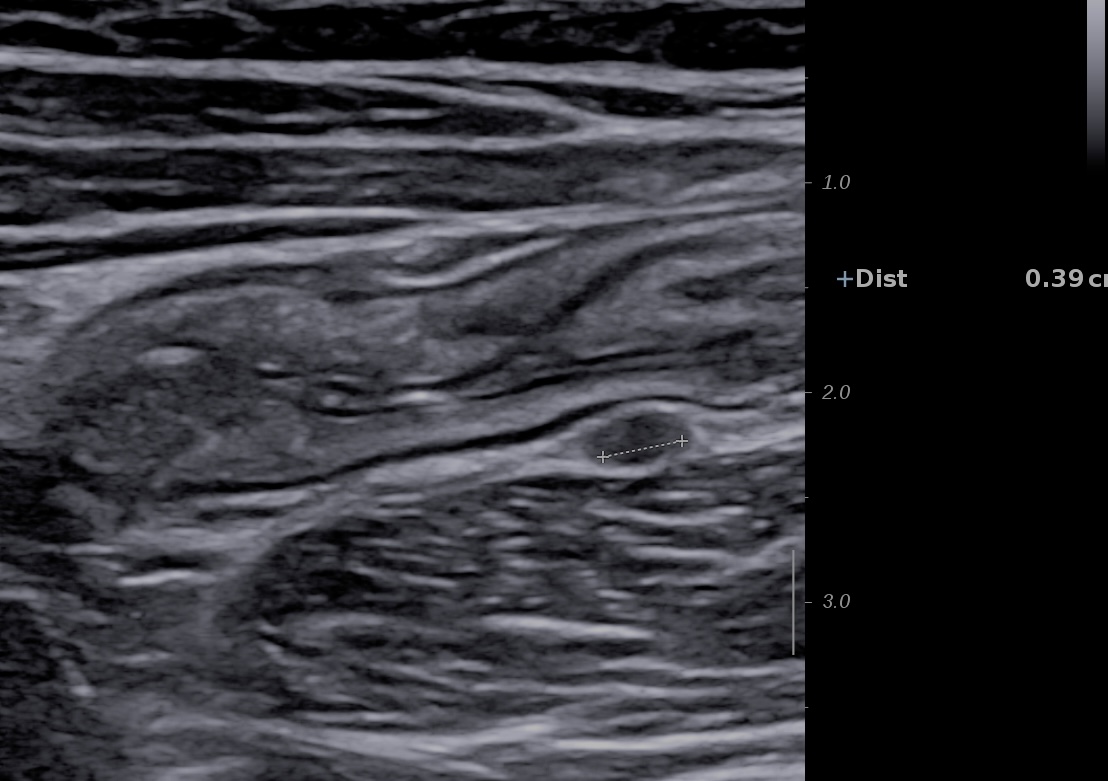

Ci-dessous RCH sigmoïde avec sous muqueuse très hyperéchogène, petit ganglion (3 mm) satellite posé sur le psoas